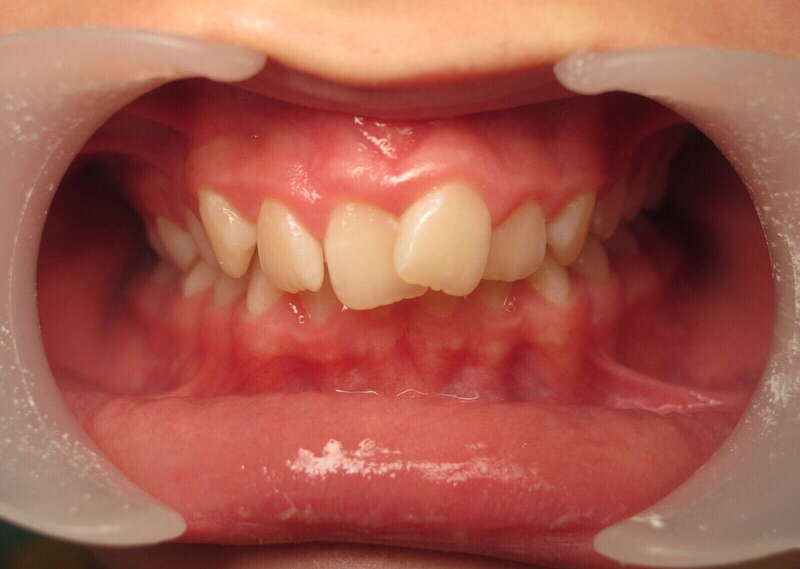

Cas n°1 traité par aligneurs (interception) - enfant

Ce cas d’interception chez un enfant de 8 ans démontre l'efficacité des aligneurs pour corriger des troubles fonctionnels précoces. Le diagnostic présentait des inversions d'articulé provoquant une déviation de la mandibule vers la gauche et un décalage des milieux.

Grâce à une coopération exemplaire et un traitement totalement indolore, l'expansion de l'arcade a permis de recentrer la mâchoire. Cette intervention a littéralement remis la croissance sur les rails, neutralisant le risque d'asymétrie faciale squelettique.

Avant

Après